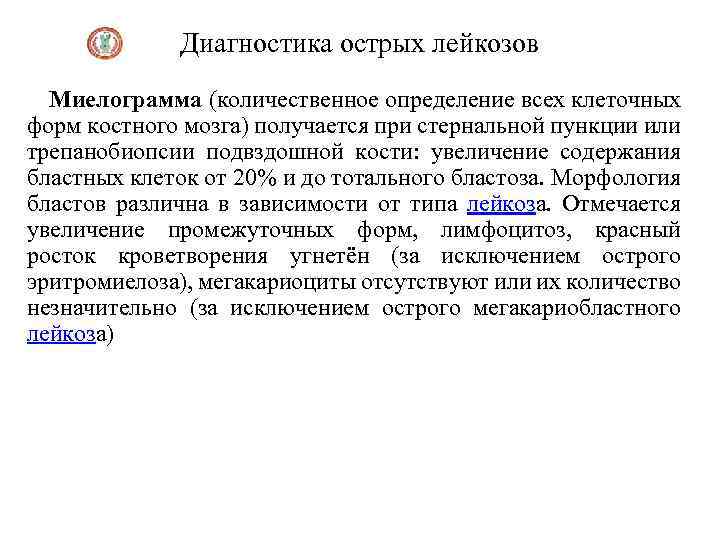

Диагностика острых лейкозов Миелограмма (количественное определение всех клеточных форм костного мозга) получается при стернальной пункции или трепанобиопсии подвздошной кости: увеличение содержания бластных клеток от 20% и до тотального бластоза. Морфология бластов различна в зависимости от типа лейкоза. Отмечается увеличение промежуточных форм, лимфоцитоз, красный росток кроветворения угнетён (за исключением острого эритромиелоза), мегакариоциты отсутствуют или их количество незначительно (за исключением острого мегакариобластного лейкоза)